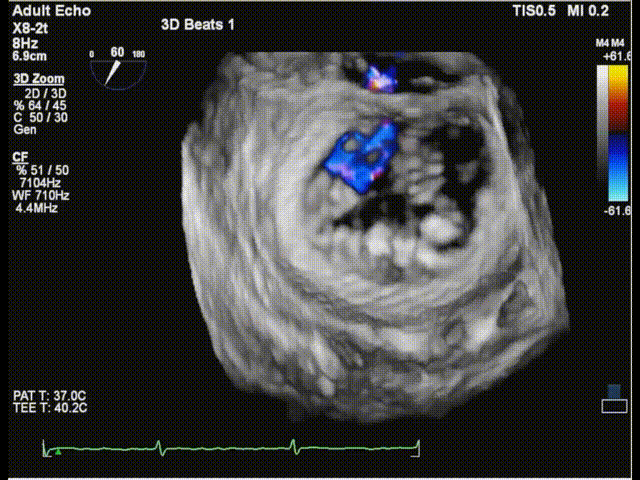

二尖瓣3Dcolor

三尖瓣反流以膈叶脱垂为主,反流主要集中在前叶和膈叶间,从中心区向边缘区的蔓延。后叶又有分了两个叶,分型上属于IIIb型的三尖瓣反流。

三尖瓣膈叶前叶

三尖瓣膈叶前叶color